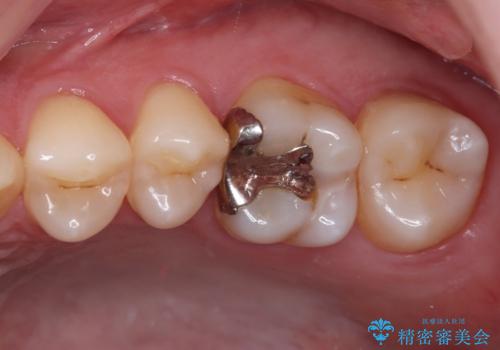

- 数年前他院にて治療した銀歯をやり替え希望の患者様です。

拡大鏡下で、銀歯、むし歯の除去を行い、セラミックインレーに適した形に整えました。